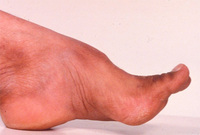

Xantoma tendíneo observado na xantomatose cerebrotendinosa

Do acervo do Dr. S. H. Subramony, com agradecimento a Dr. Uday Muthane; usado com permissão